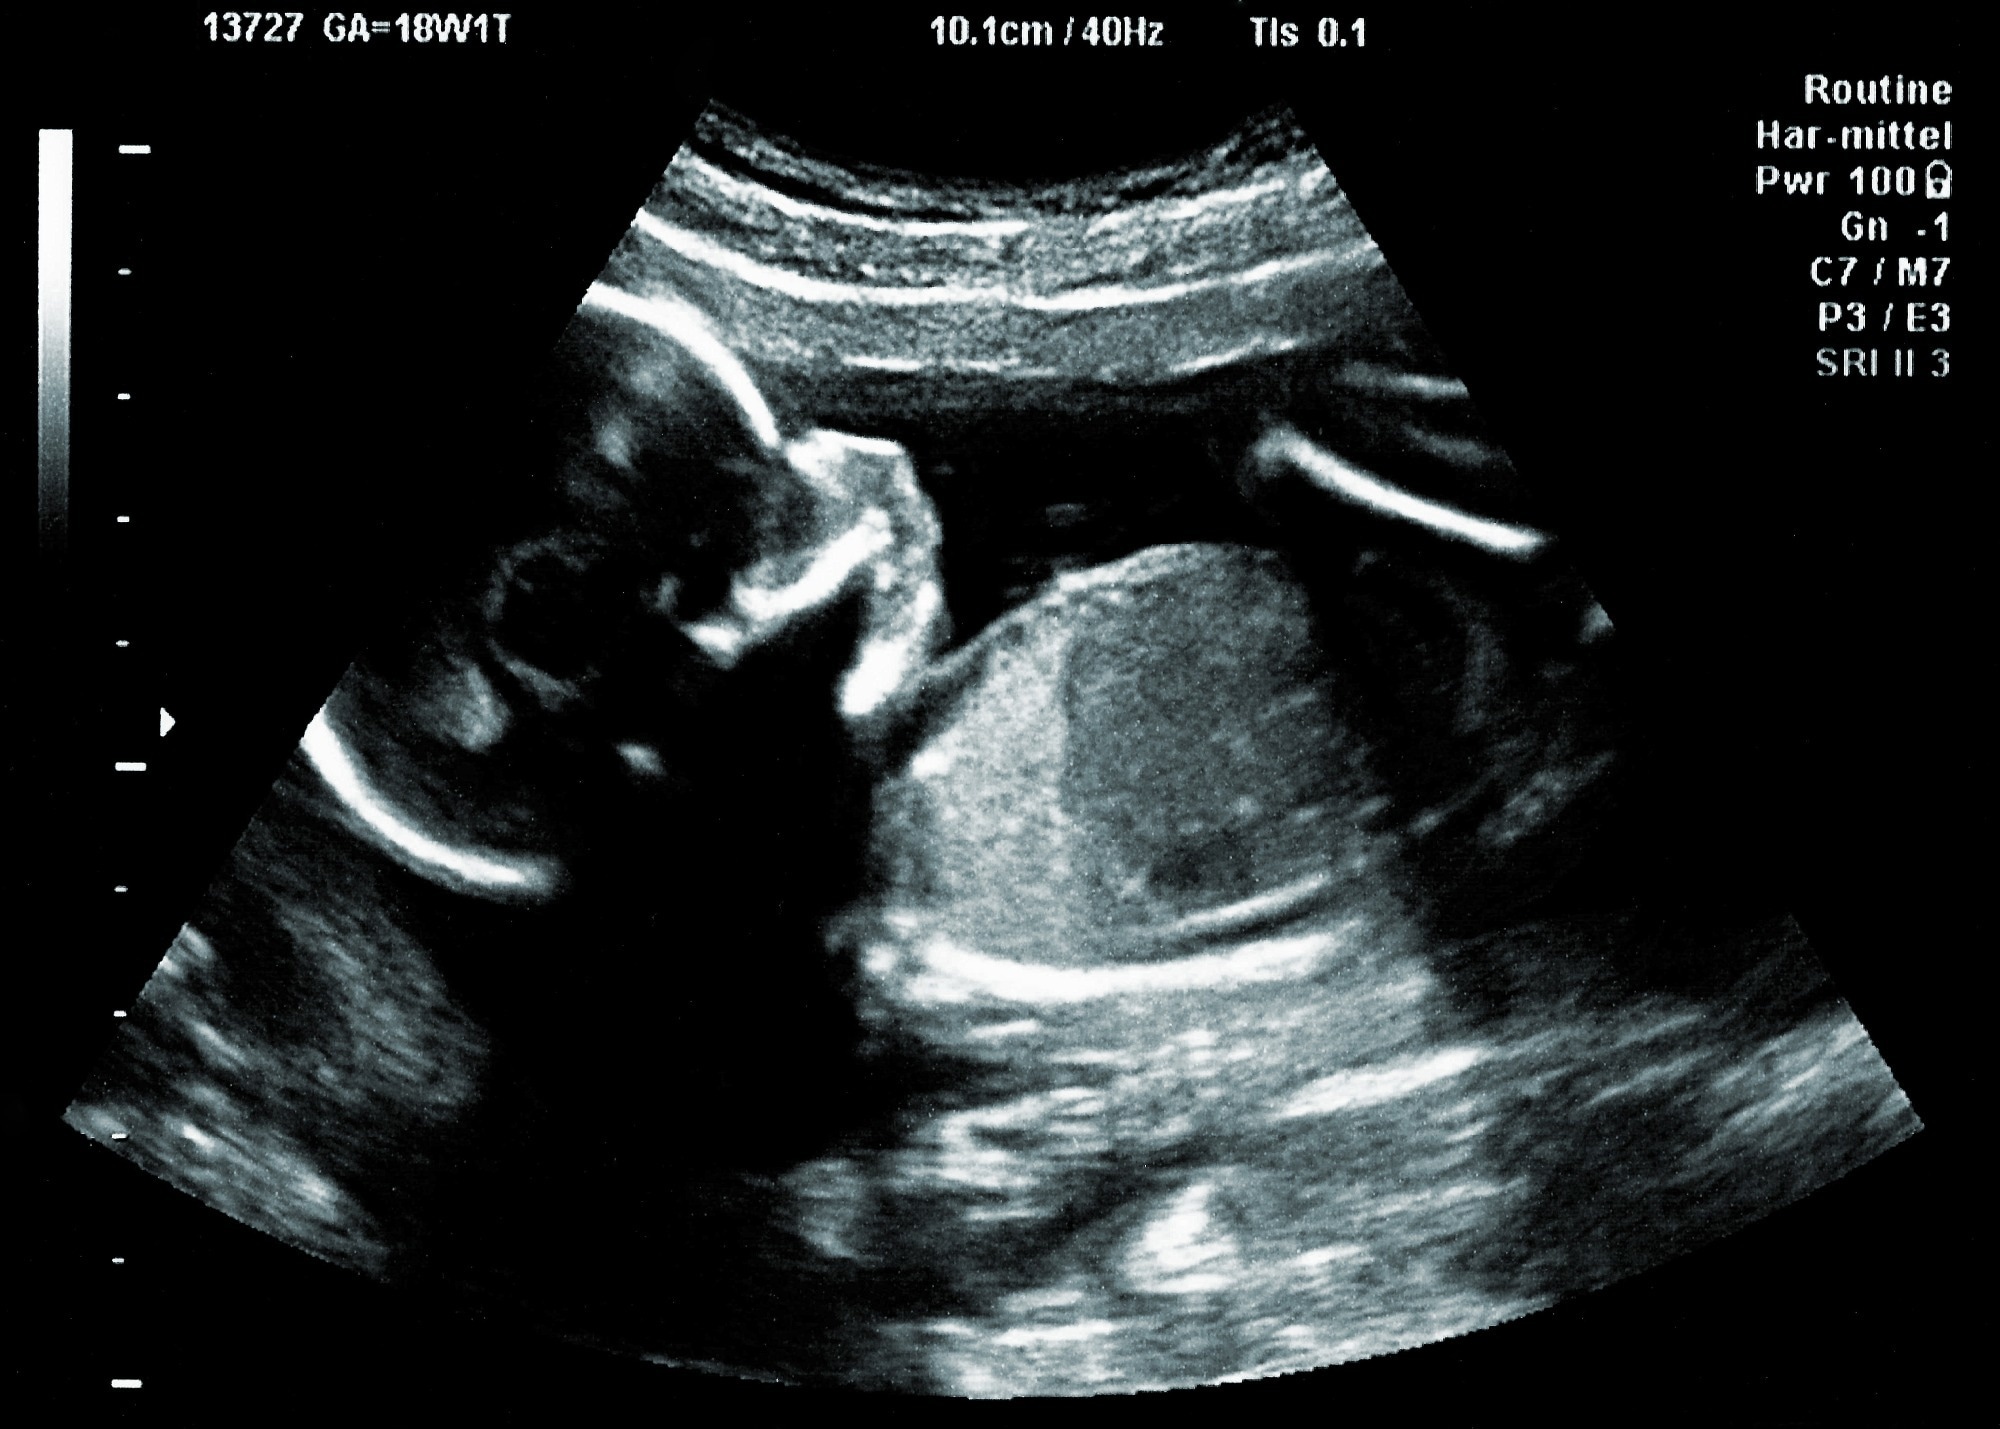

מחקר שחוקר שיטות בדיקה לסוכרת הריונית מצביע על כך שלמעלה ממחצית מהנשים ההרות עם המצב אינן מאובחנות עם תהליך בדיקת